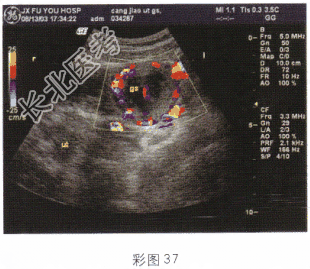

- 单项选择题女性,27岁, 停经48天,阴道不规则出血6天; 血HCG70μg/ml。结合超声图像(彩图37),最可能的诊断是

D、异位妊娠